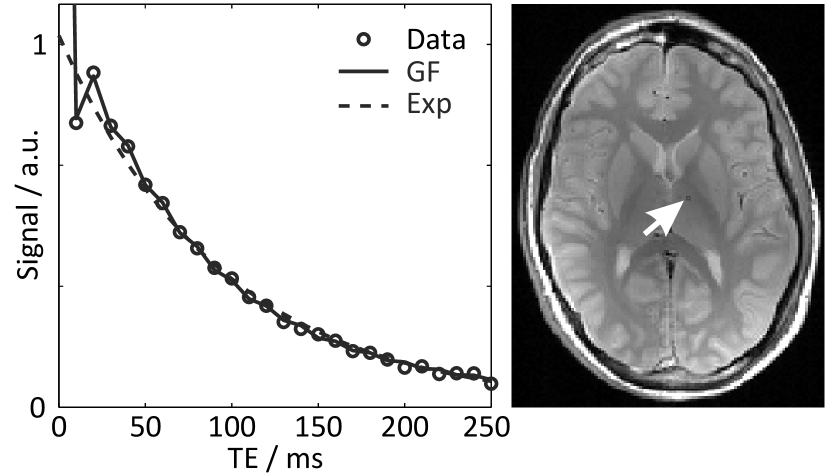

T2 mapping relies on a train of successively refocused spin echoes. In practical MRI, however, the assumption that these signals represent the true T2 relaxation decay is violated due to the formation of indirect echoes [16, 17]. The most notable consequence is a hypointense first spin echo which clearly disrupts the expected mono-exponential signal decay. A variety of attempts to better reproduce the echo amplitudes employ the EPG algorithm [18, 19, 20, 21] which considers different magnetization pathways in a recursive description. In 2007 Lukzen et al. [11] obtained an explicit analytical expression for the problem by exploiting the generating function (GF) formalism [22, 23]. In contrast to the EPG algorithm, the model formula can be implemented very efficiently using the fast Fourier transform. An example of the improved performance for an extended GF model [12] which includes non-ideal slice profiles is shown in Fig. 1 for human brain MRI data.

Given a series of magnitude images from a MSE train, the GF approach can be used to determine quantitative T2 values at different spatial positions by pixel-wise fitting. The method has been demonstrated to yield more accurate T2 estimations than a mono-exponential fit [12]. As a potential limitation, (2) requires a valid T1 and B1 map prior to T2 reconstruction as well as an estimation of the pulse profile in slice direction. The influence of errors in these estimates on the reconstructed T2 maps has previously been elaborated for fully sampled data [12].